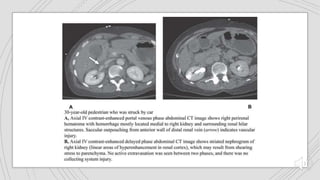

Grade I Grade II Grade III Grade IV Grade V

Are deeper lacerations

(>1cm) that do not result in

urine leak. Any injury

occurring in the presence

of a vascular injury

Vascular injuries include

pseudoaneurysm or

arteriovenous fistula.

described as a focal

collection of vascular

contrast enhacement that

shows decreasing

attenuation with delayed

imaging